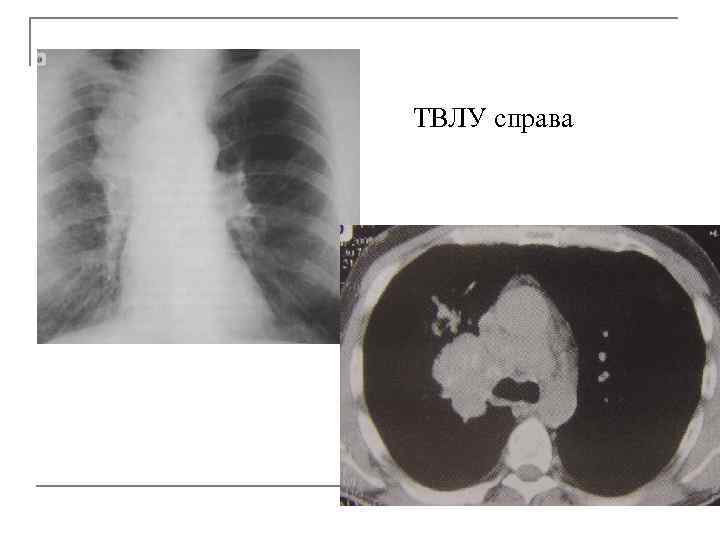

ТВЛУ справа

Осложнения ТВЛУ q гематогенная или лимфогенная диссеминация, q плеврит, q сдавление прилежащего бронха с развитием обтурационного ателектаза, вокруг суженного бронха выявляется конгломерат увеличенных л/узлов (чаще у детей и подростков). У пациентов старше 40 лет дифференцируем с центральным раком легкого. q. Верификация природы поражения в корне возможна при гистологическом исследовании после ФБС. q. Однако, протяженность поражения и степень сужения осуществляется при КТ более детально.

Основные КТ признаки q Увеличение л/узлов обычно бронхо-пульмональной группы в корне одного легкого и, как правило, выше расположенные л/узлы средостения. q Расширение корня, полицикличные контуры. q Утолщение междолькового интерстиция в прилежащей к корню легочной ткани. q Двухсторонние изменения корней не типичны для этой формы туберкулеза!